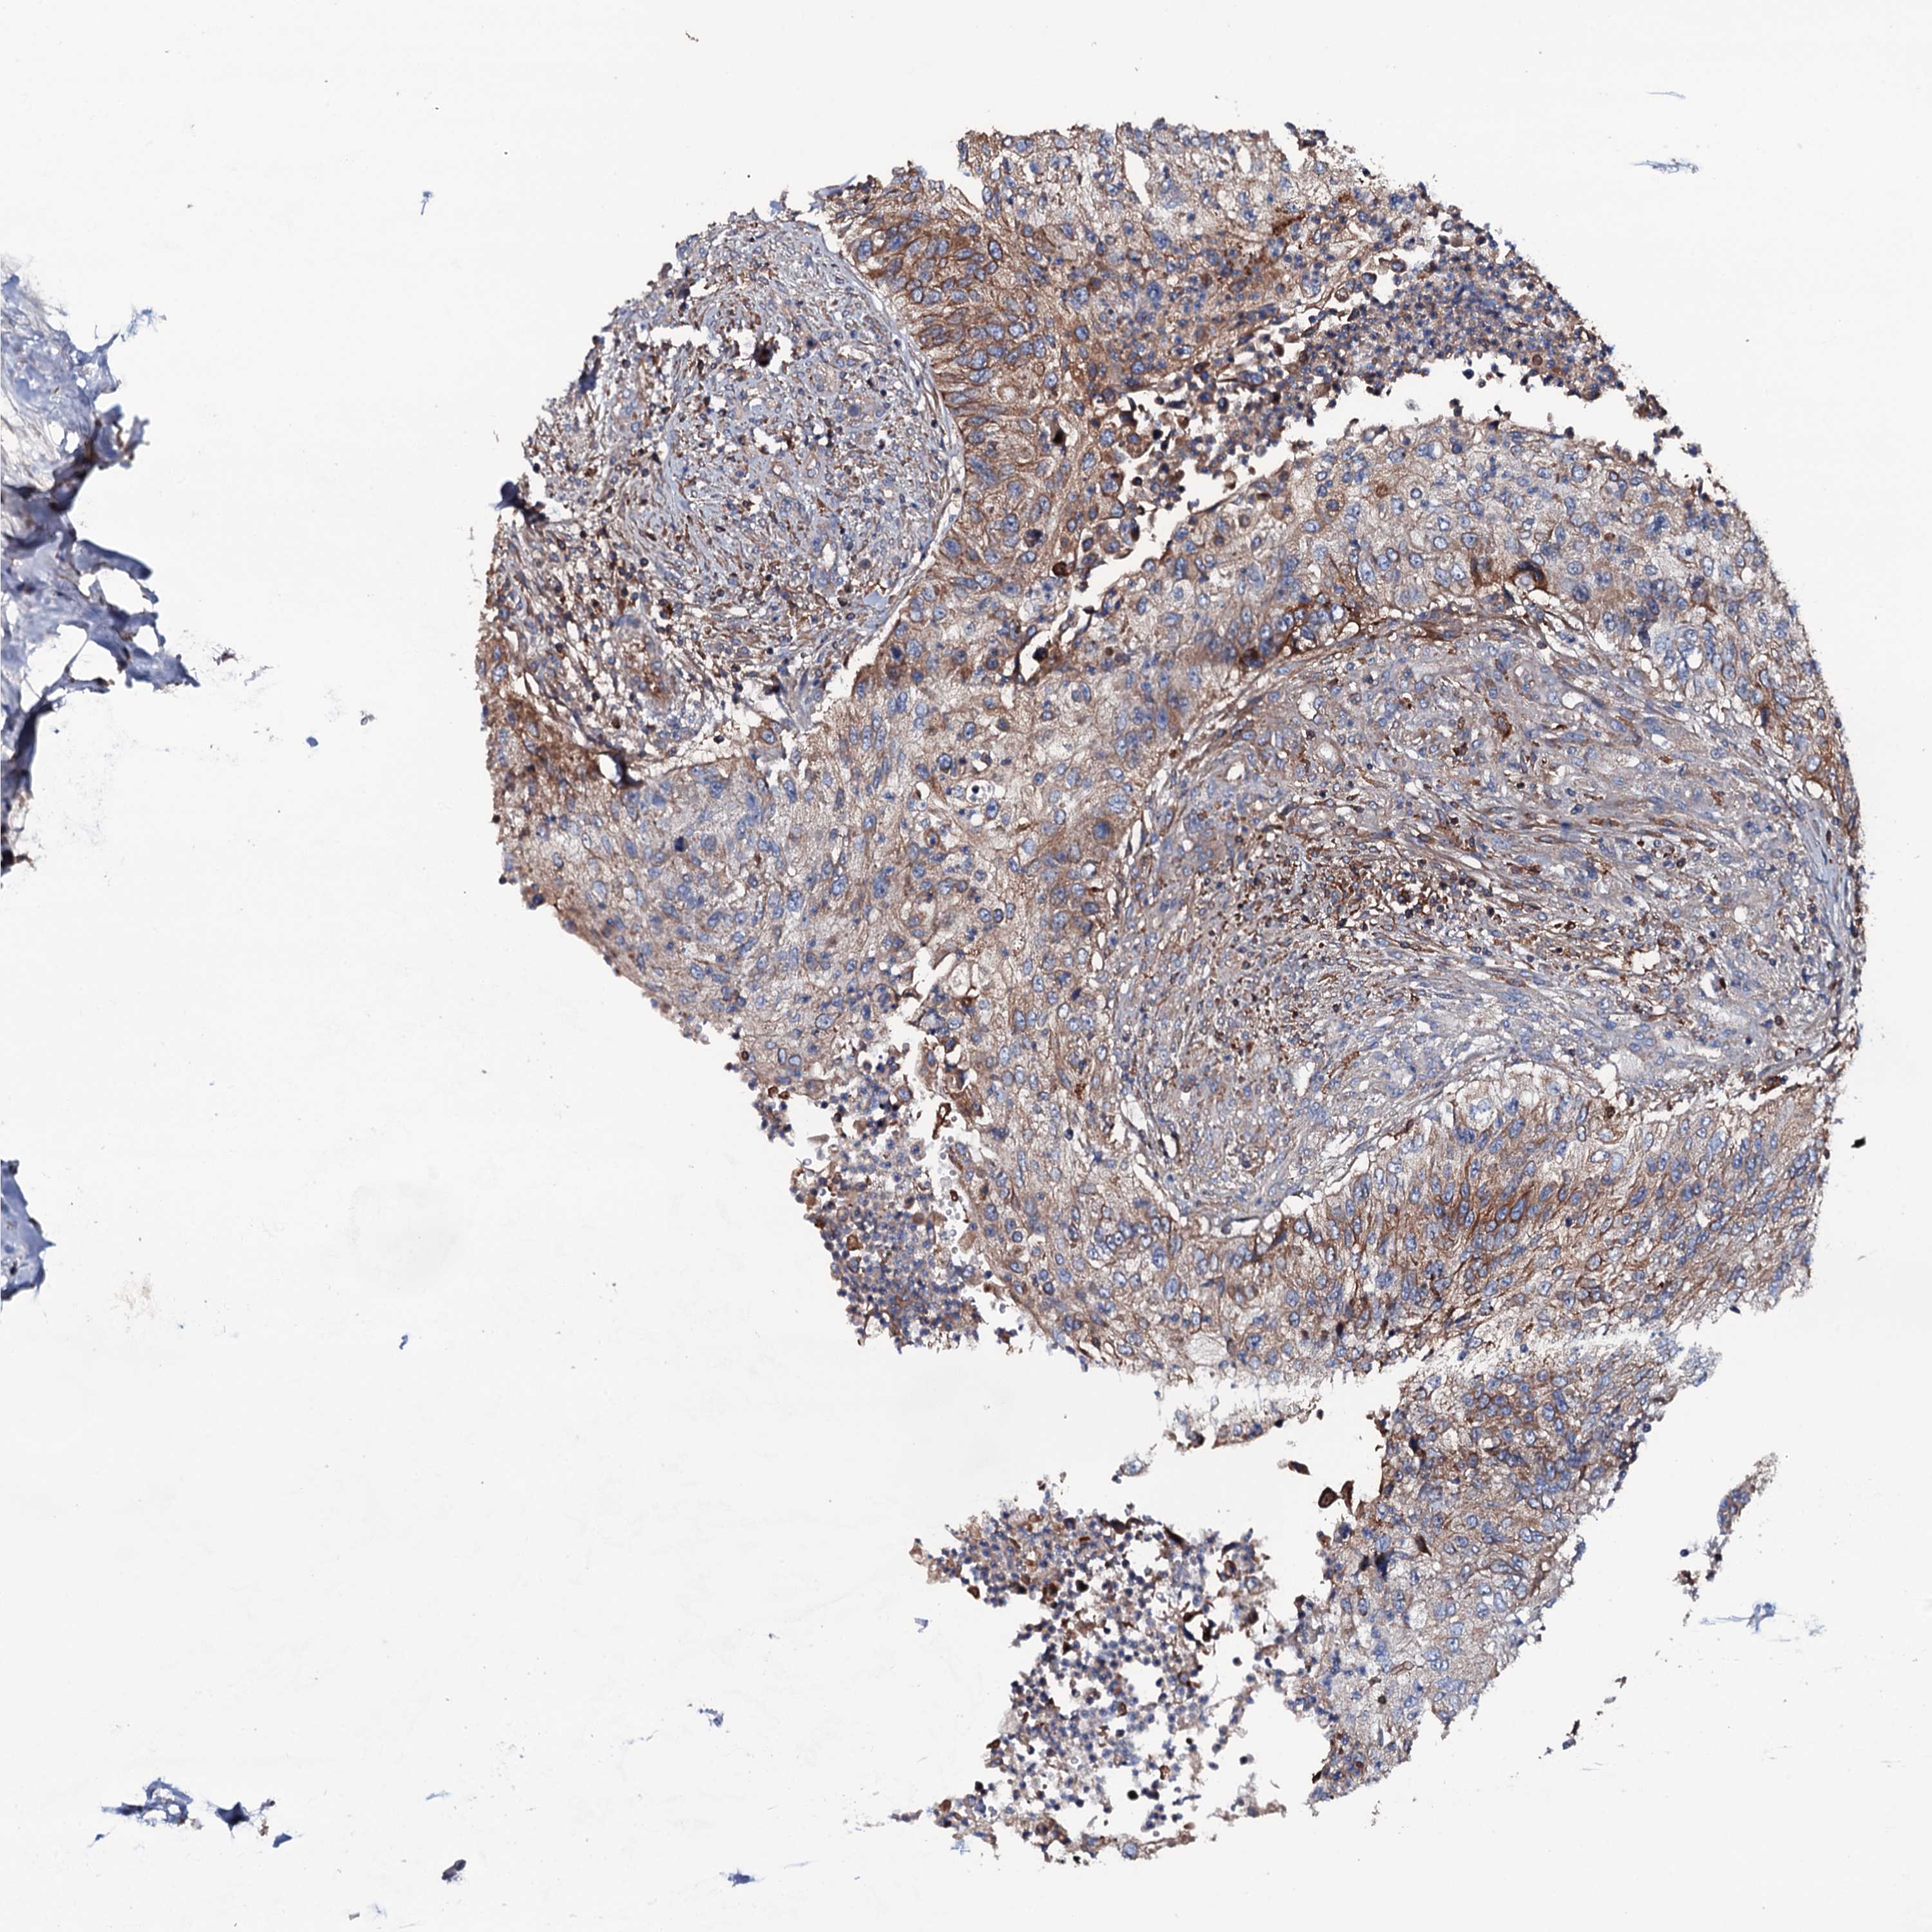

UROTHELIAL CANCER - Protein expressioni

A mouse-over function shows sample information and annotation data. Click on an image to view it in a full screen mode. Samples can be filtered based on level of antibody staining by selecting one or several of the following categories: high, medium, low and not detected. The assay and annotation is described here.

Note that samples used for immunohistochemistry by the Human Protein Atlas do not correspond to samples in the TCGA dataset.

Antibody stainingi

Antibody staining in the annotated cell types in the current human tissue is reported as not detected, low, medium, or high, based on conventional immunohistochemistry profiling in selected tissues. This score is based on the combination of the staining intensity and fraction of stained cells.

Each image is clickable and will lead to virtual microscopy that enables deeper exploration of all samples and also displays staining intensity scores, fraction scores and subcellular localization as well as patient and tissue information for each sample.

Antibody HPA020873

Antibody HPA040413

Staining

High

Medium

Low

Not detected

Intensity

Strong

Moderate

Weak

Negative

Quantity

>75%

75%-25%

<25%

None

Location

Nuclear

Cytoplasmic/membranous

Cytoplasmic/membranous,nuclear

Urothelial carcinoma, High grade

Urothelial carcinoma, Low grade

Urothelial carcinoma, NOS